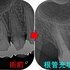

何とか保存出来た外部吸収

以前ブログにさせてもらった。

術前

根管充填後

術後1年

痛みや腫れも出ておらず使えているようです。

ホント外部吸収の治療は困難を極めるのと、持つまでの治療となってしまいますが何とか保存出来てよかったです!